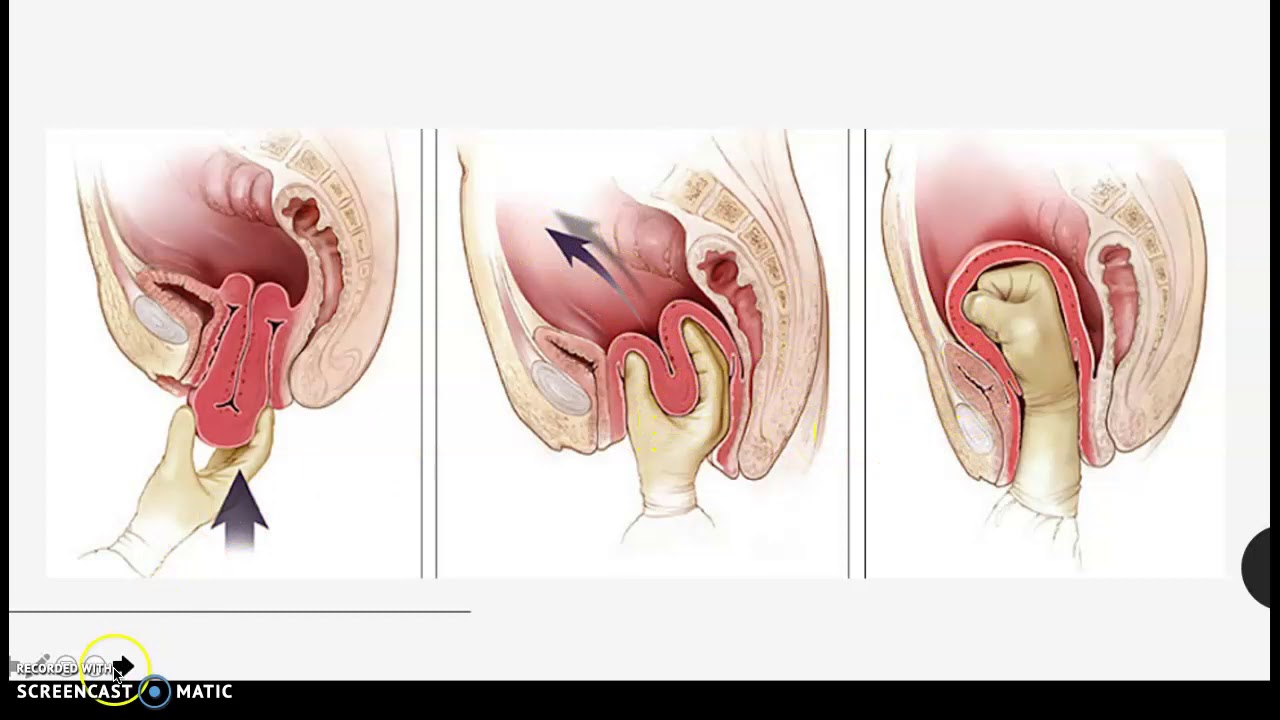

Омоложение влагалища

«Омоложение влагалища» включает в себя компоненты перинеопластики и вагинопластики и проводится для лечения «широкого» влагалища. Эти процедуры являются не чем иным, как модификациями существующих хорошо зарекомендовавших себя методов реконструктивной хирургии влагалища и тазового дна при кольпоперинеорафии, чтобы изменить калибр влагалища за счет уменьшения диаметра влагалищного канала наряду с реконструкцией тела промежности [23].

Вагинопластика предназначена для хирургического сужения влагалищного канала и включает удаление избыточной слизистой оболочки влагалища из сводов влагалища.Он может включать переднюю кольпорафию, заднюю кольпорафию, иссечение латеральной слизистой оболочки влагалища или различные комбинации этих хирургических методов (рис.). Некоторые хирурги также проводят пластику леватора по средней линии, чего, по нашему мнению, лучше всего избегать, так как это может вызвать выраженную диспареунию.

Перинеопластика , также известная как перинеоррафия, включает хирургическую реконструкцию влагалищного входа путем подтягивания мышц промежности и влагалища с целью уменьшения размера влагалищного отверстия.Часто выполняется вместе с задней кольпорафией, это называется кольпоперинеорафией. Обратная перинеопластика включает в себя реконструкцию рубцовой ткани, вызванной склеротическим лишаем, или предшествующая операция предназначена для лечения диспареунии и включает в себя разрез пальпируемых полос и рубца с одновременным созданием лоскута для увеличения интроитального калибра.

Хирургическая цель перинеопластики состоит в укреплении тазового дна во входе и внутри для получения приподнятой промежности, реконструкции тела промежности, внутренней подтяжки и исправления дефектов заднего отдела.Хирургическая процедура, если она выполнена правильно, восстанавливает нисходящий угол влагалища, что, в свою очередь, приводит к давлению полового члена на клиторальный комплекс, толкая его к лобковой кости с половым толчком, предположительно помогая с клиторальным оргазмом.

Омоложение влагалища

«Омоложение влагалища» включает в себя компоненты перинеопластики и вагинопластики и проводится для лечения «широкого» влагалища. Эти процедуры являются не чем иным, как модификациями существующих хорошо зарекомендовавших себя методов реконструктивной хирургии влагалища и тазового дна при кольпоперинеорафии, чтобы изменить калибр влагалища за счет уменьшения диаметра влагалищного канала наряду с реконструкцией тела промежности [23].

Вагинопластика предназначена для хирургического сужения влагалищного канала и включает удаление избыточной слизистой оболочки влагалища из сводов влагалища.Он может включать переднюю кольпорафию, заднюю кольпорафию, иссечение латеральной слизистой оболочки влагалища или различные комбинации этих хирургических методов (рис.). Некоторые хирурги также проводят пластику леватора по средней линии, чего, по нашему мнению, лучше всего избегать, так как это может вызвать выраженную диспареунию.

Перинеопластика , также известная как перинеоррафия, включает хирургическую реконструкцию влагалищного входа путем подтягивания мышц промежности и влагалища с целью уменьшения размера влагалищного отверстия.Часто выполняется вместе с задней кольпорафией, это называется кольпоперинеорафией. Обратная перинеопластика включает в себя реконструкцию рубцовой ткани, вызванной склеротическим лишаем, или предшествующая операция предназначена для лечения диспареунии и включает в себя разрез пальпируемых полос и рубца с одновременным созданием лоскута для увеличения интроитального калибра.

Хирургическая цель перинеопластики состоит в укреплении тазового дна во входе и внутри для получения приподнятой промежности, реконструкции тела промежности, внутренней подтяжки и исправления дефектов заднего отдела.Хирургическая процедура, если она выполнена правильно, восстанавливает нисходящий угол влагалища, что, в свою очередь, приводит к давлению полового члена на клиторальный комплекс, толкая его к лобковой кости с половым толчком, предположительно помогая с клиторальным оргазмом.